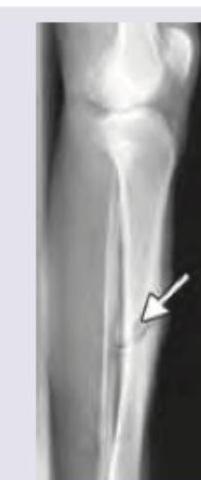

Identify the fracture shown in the image below:

Explanation: ***Fracture tibia*** - The image displays a **long bone fracture** in the lower leg, characterized by a visible fracture line (indicated by the arrow) through the shaft. - The upper part of the image clearly shows the **knee joint**, confirming this as a view of the tibia (shin bone). *Fracture radius* - The radius is a bone in the **forearm**, not the lower leg. - The image clearly depicts the **lower extremity** with a knee joint visible. *Colle's fracture* - A Colles' fracture is a specific type of fracture of the **distal radius** (near the wrist), which is in the forearm. - The fracture shown is in the **tibia**, a bone of the lower leg, and the location is not characteristic of a Colles' fracture. *Supracondylar fracture humerus* - The humerus is the **upper arm bone**, and a supracondylar fracture occurs near the elbow joint. - The image shows a fracture in the **lower leg**, specifically the tibia, not the upper arm.